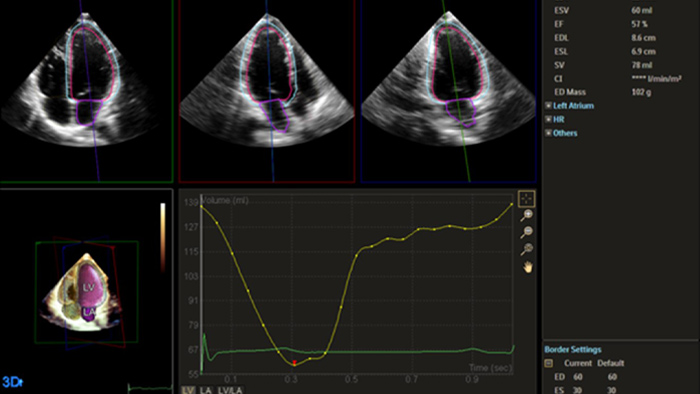

Image showing results of automation for robust, proven reproducible cardiac quantification in both 2D and 3D

Automation for robust, proven reproducible cardiac quantification in both 2D and 3D.

Image showing quantification through Philips Dynamic HeartModel

Quantification through Dynamic HeartModel.